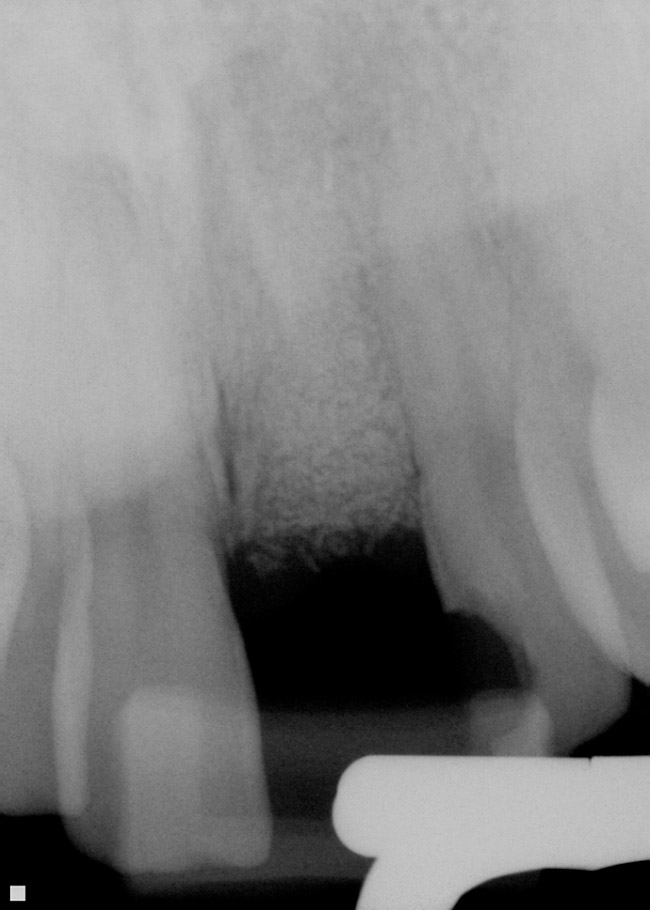

Alveolele postextracţionale au fost lăsate să se vindece pentru o perioadă medie de 6 luni. După vindecare, s-au inserat în total 109 implante. Nu s-au înregistrat eşecuri de grefare şi implantele au fost aplicate în toate cele 109 locaţii grefate. Un total de 58 de implante au fost introduse cu reflecţia lamboului, iar 51 cu tehnica fără lambou/prin perforare. S-au folosit implante endoosoase într-o singură etapă şi în două etape, reprezentând diferite forme de implante. Diametrele implantelor au variat de la 3,3mm până la 5mm, cu lungimea implantelor variind între 10-15mm, în funcţie de consideraţiile restauratoare şi localizările în cadrul alveolelor. Toate implantele inserate aveau design cu suprafaţă rugoasă. Din cele 109 implante inserate, 67 au fost aplicate la maxilar şi 42 la mandibulă. Un total de 33 de implante au fost inserate la fumători (11 pacienţi) şi 76 de implante la nefumători (58 pacienţi).

Din cele 109 implante inserate la cei 69 pacienţi în cursul unei perioade de 4 ani, nu s-a înregistrat niciun eşec implantologic după inserţia dispozitivelor fixe şi restaurarea protetică ulterioară. La descoperirea implantelor, nu erau semne de mobilitate a acestora, şi toate implantele inserate au fost restaurate. În momentul prelucrării datelor, toate implantele au rămas complet încărcate şi în funcţiune, rezultând o rată de supravieţuire de 100% (tabelul 1). Ca şi grup, implantele erau funcţionale şi încărcate de o perioadă medie de 2 ani, variind între 6-65 luni. Indiferent de tipul implantului, localizarea în alveolă, statusul de fumător, 100% din implante sunt în funcţiune şi actualmente (tabelul 1 şi fig. 1-9).